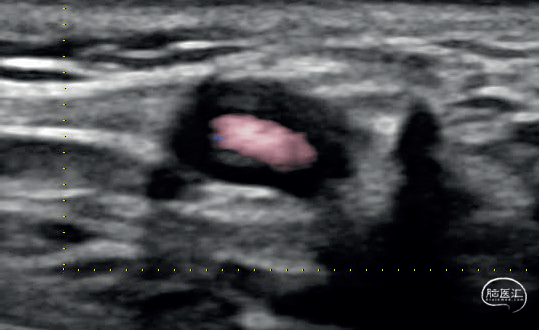

动脉超声因其成本低、普及广且无辐射暴露而常被早期使用;但其操作者间变异性较高,需要具备该领域的专业知识。推荐将双侧颞动脉和腋动脉超声作为疑似巨细胞动脉炎的首选影像学检查方法,其汇总敏感性估计为88%,特异性为96%。急性动脉炎症的典型表现为不可压缩的晕征(图2),即均匀的低回声环形管壁增厚,且探头压迫下不消失。尽管并非病征性,但颞动脉和腋动脉同时出现晕征可增强超声对巨细胞动脉炎的诊断性能。动脉超声在大动脉炎中也可能有用,特别是在检测结构性病变方面。除胸降主动脉外,大多数动脉(如颈动脉、椎动脉、锁骨下动脉、肠系膜动脉和肾动脉)都可通过超声检查,但随着动脉位置加深,分辨率会下降。

图2.超声显示的巨细胞动脉炎动脉炎症。动脉超声是一种成本低廉且广泛普及的检查技术,目前被推荐作为疑似巨细胞动脉炎的首选影像学检查方法。该技术能有效检测结构性病变和血管壁炎症性改变,例如颞动脉(A)与腋动脉(B)中显示的不可压缩性晕征。晕征表现为均匀的低回声环形管壁增厚,在探头加压时不会消失,虽非病征性表现,但具有较好的诊断准确性: